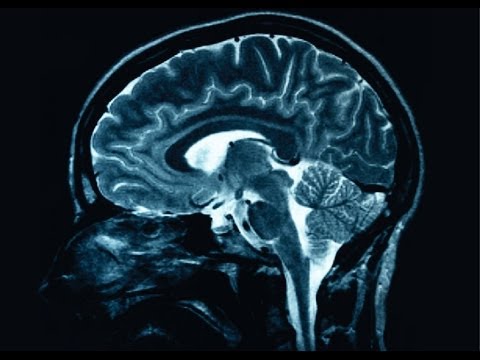

Popovičův Mozak aneb dokážeme zmapovat myšlenky?

Popis činnosti profesora Washingtonské univerzity Zorana Popoviče, který se kromě vývoje systému technologické podpory výuky věnuje vědeckému poznávání funkce mozku na úrovni jednotlivých neuronů a…